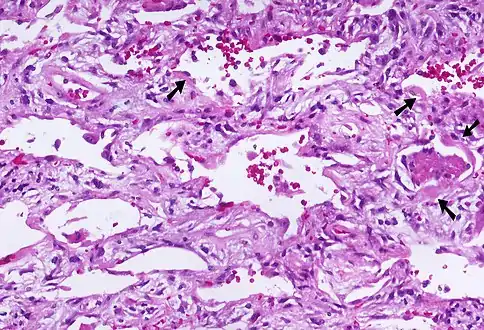

| Micrograph of diffuse alveolar damage, the histologic correlate of acute interstitial pneumonitis. H&E stain. | |

Rapid progression from initial symptoms to respiratory failure is a key feature. An X-ray that shows ARDS is necessary for diagnosis (fluid in the small air sacs (alveoli) in both lungs). In addition, a biopsy of the lung that shows organizing diffuse alveolar damage is required for diagnosis. This type of alveolar damage can be attributed to nonconcentrated and nonlocalized alveoli damage, marked alveolar septal edema with inflammatory cell infiltration, fibroblast proliferation, occasional hyaline membranes, and thickening of the alveolar walls. The septa are lined with atypical, hyperplastic type II pneumocytes, thus leading to the collapse of airspaces. Other diagnostic tests are useful in excluding other similar conditions, but history, X-ray, and biopsy are essential. These other tests may include basic blood work, blood cultures, and bronchoalveolar lavage. The clinical picture is similar to ARDS, but AIP differs from ARDS in that the cause for AIP is not known.

Acute interstitial pneumonia (AIP)/Idiopathic DAD